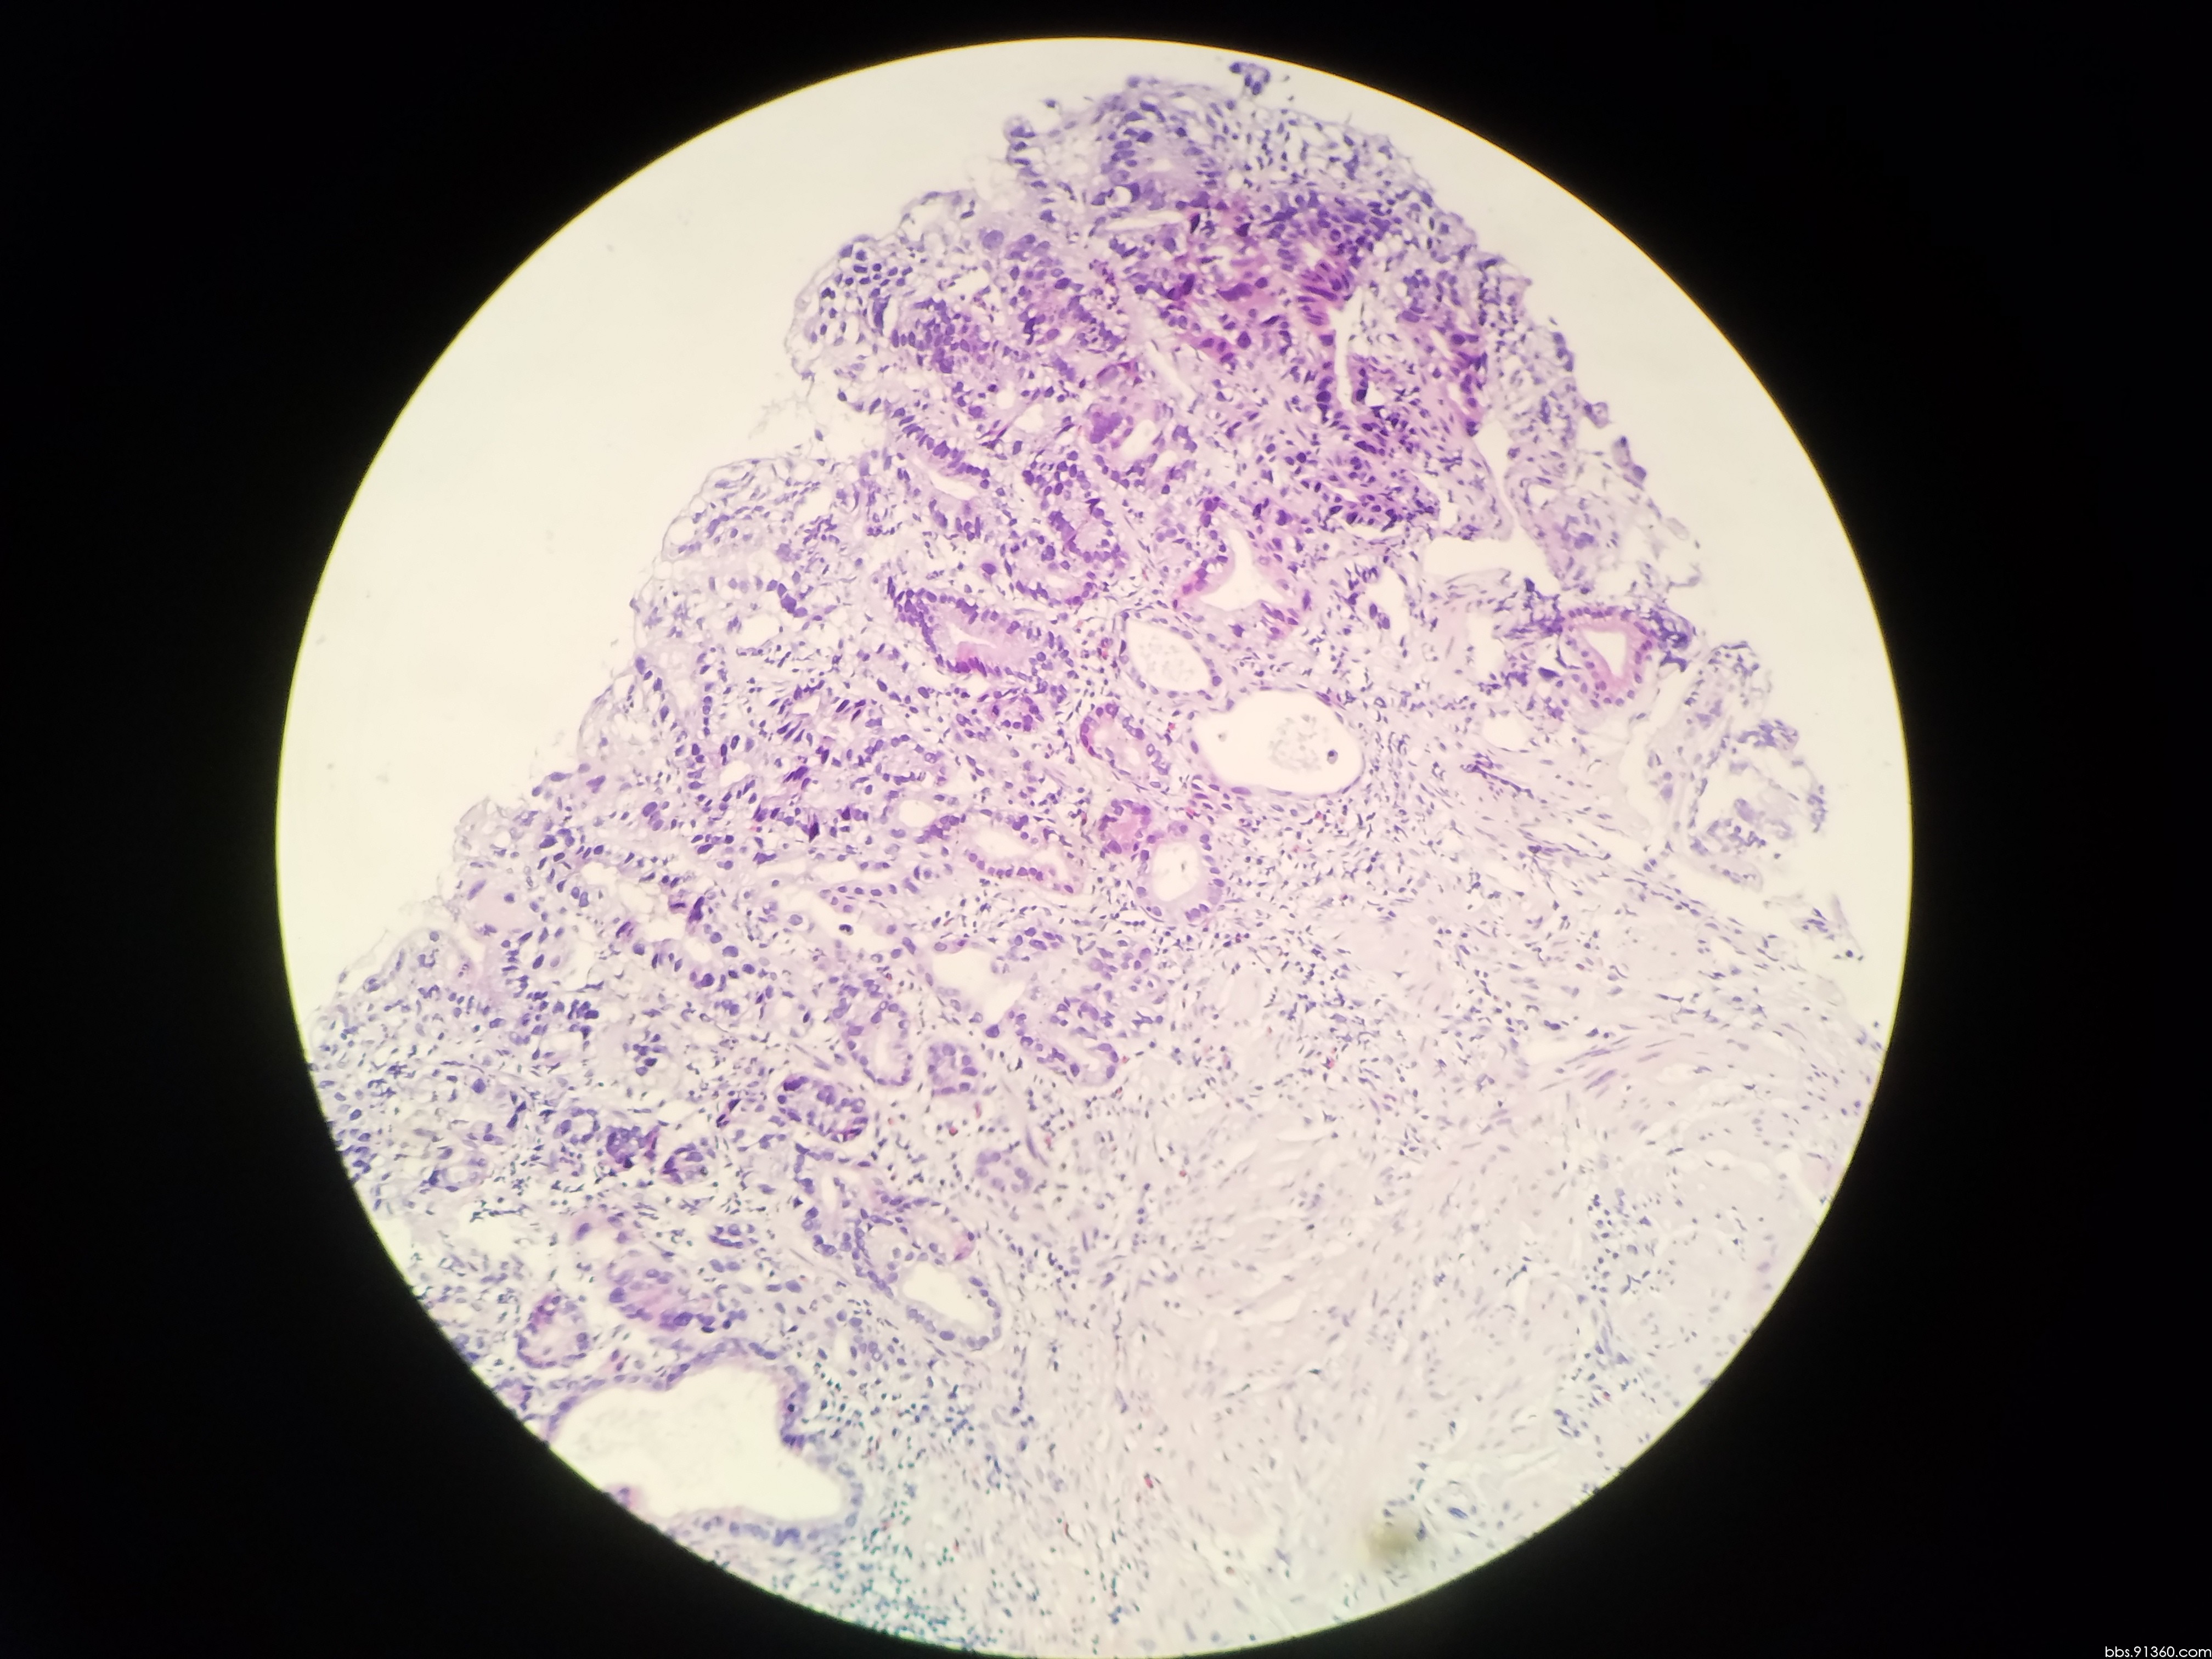

胃窦活检

图片尺寸600x800